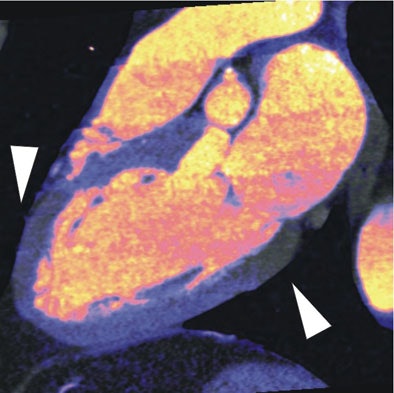

| In a 64-year-old man presenting with chest pain, 3D and multiplanar reconstructions of coronary CTA images show a significant stenosis in the first diagonal branch of the left anterior descending (LAD) artery and a 70% stenosis in the mid right circumflex artery (RCA) (arrows). All images courtesy of Dr. Balázs Ruzsics, Ph.D., and Dr. U. Joseph Schoepf. |